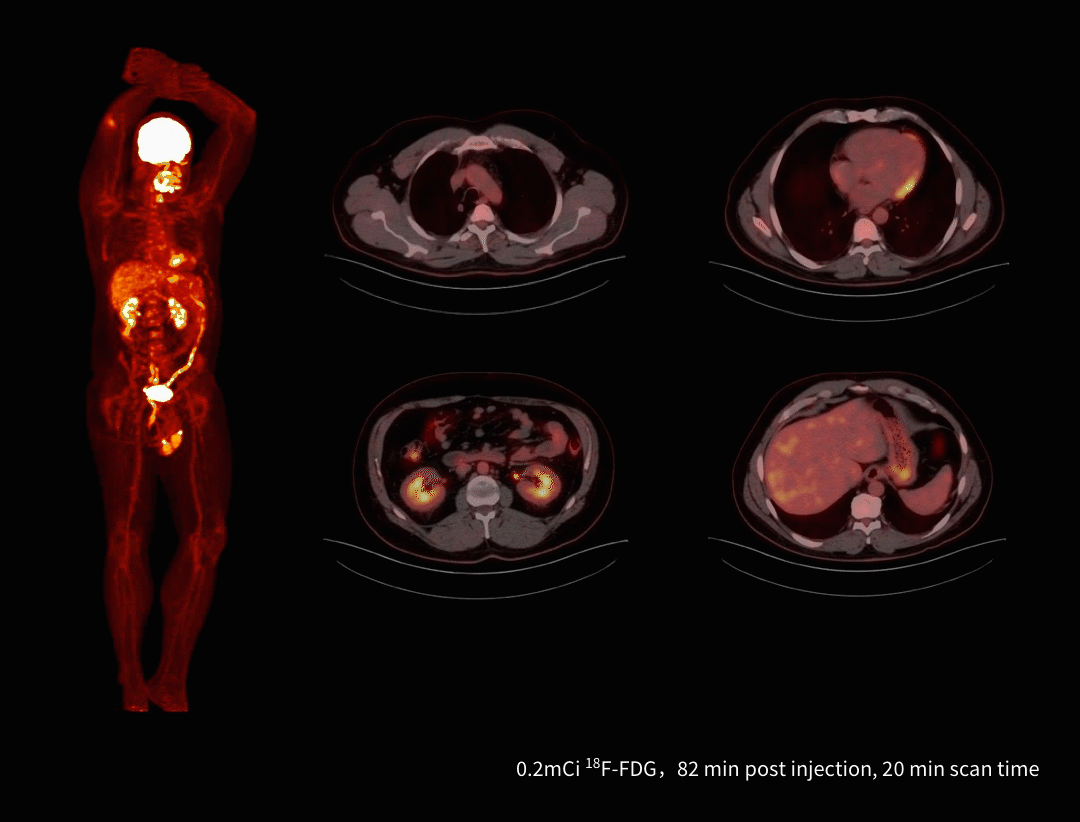

Imagistică PET/CT cu doză redusă de radiotrasor

uEXPLORER permite scanări whole-body de înaltă calitate utilizând doze mult reduse de radiotrasor – doar 0,2 mCi pentru un pacient de 100 kg (≈0,002 mCi/kg), semnificativ mai mic față de doza tipică de 0,08–0,15 mCi/kg. Această performanță minimizează expunerea pacientului, menținând în același timp o calitate superioară a imaginii.